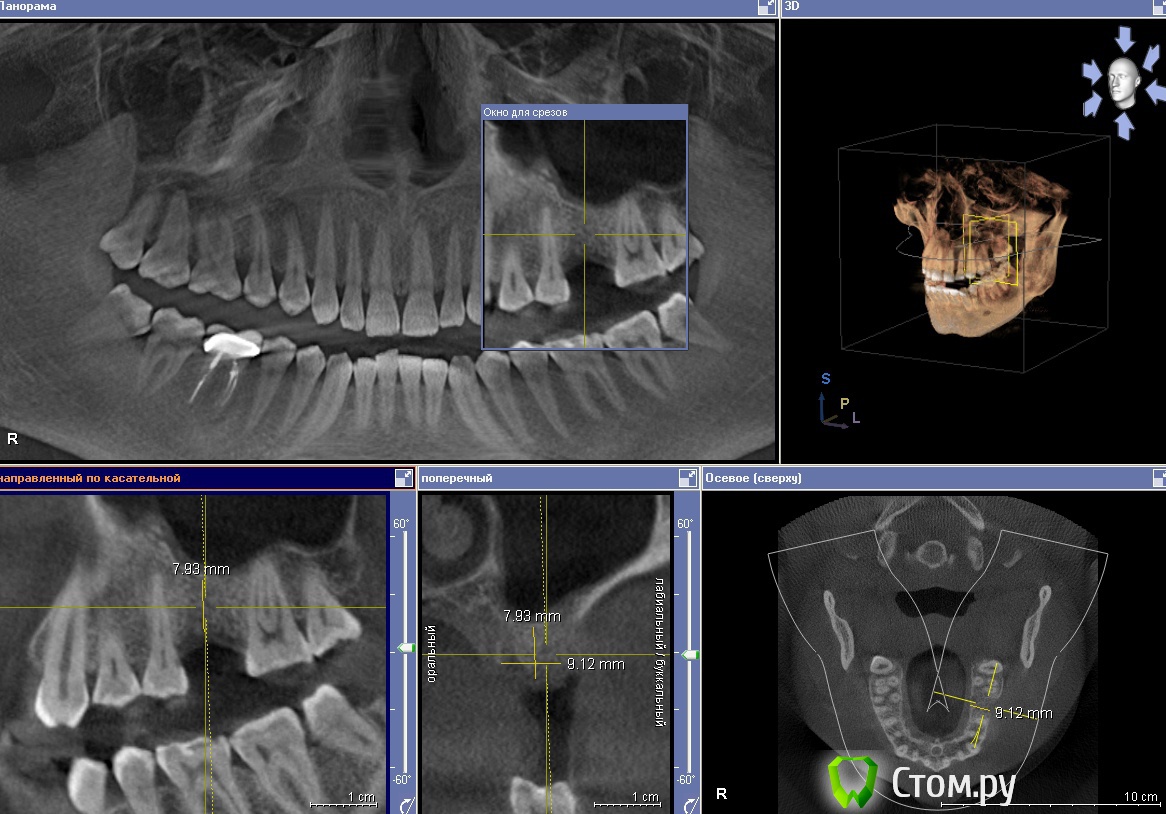

g_kot Опубликовано 31 мая, 2014 Автор Поделиться Опубликовано 31 мая, 2014 (изменено) Добрый всем день. Сделал КТ. Ваше мнение. Мне говорят про открытый синус. Закрытым не обойтись? А на втором снимке кариес? Изменено 31 мая, 2014 пользователем g_kot Ссылка на комментарий

IvanK Опубликовано 31 мая, 2014 Поделиться Опубликовано 31 мая, 2014 можно и закрытым обойтись Ссылка на комментарий

red_butler Опубликовано 31 мая, 2014 Поделиться Опубликовано 31 мая, 2014 (изменено) + 1 к за крытому синуслифтингу, но бывает что доктор делает так как у него лучше получается или больше нравится. Изменено 31 мая, 2014 пользователем red_butler 1 Ссылка на комментарий

g_kot Опубликовано 31 мая, 2014 Автор Поделиться Опубликовано 31 мая, 2014 Спасибо. Еще раз поговорю про это со своим доктором. А что скажете про темное место между 7 и 8 на втором снимке. Кариес??? или такая форма зуба возможна? Ссылка на комментарий

faity Опубликовано 31 мая, 2014 Поделиться Опубликовано 31 мая, 2014 Спасибо. Еще раз поговорю про это со своим доктором. А что скажете про темное место между 7 и 8 на втором снимке. Кариес??? или такая форма зуба возможна?я бы 8-ой удалил, 7 смотреть надо после удаления, скорее всего кариес Ссылка на комментарий

g_kot Опубликовано 1 июня, 2014 Автор Поделиться Опубликовано 1 июня, 2014 (изменено) Записался к врачу... А кариес в таком месте нормально можно залечить (после удаления 8ки) или он там слишком близко к корню? Изменено 1 июня, 2014 пользователем g_kot Ссылка на комментарий

red_butler Опубликовано 1 июня, 2014 Поделиться Опубликовано 1 июня, 2014 Записался к врачу... А кариес в таком месте нормально можно залечить (после удаления 8ки) или он там слишком близко к корню?Через две три недели после удаления "восьмерки" займетесть лечением кариеса, если судить только по снимку - все вполне лечибельно Ссылка на комментарий